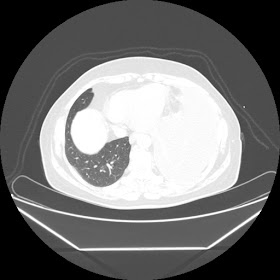

A 45 years old woman recurrent HRCT Images